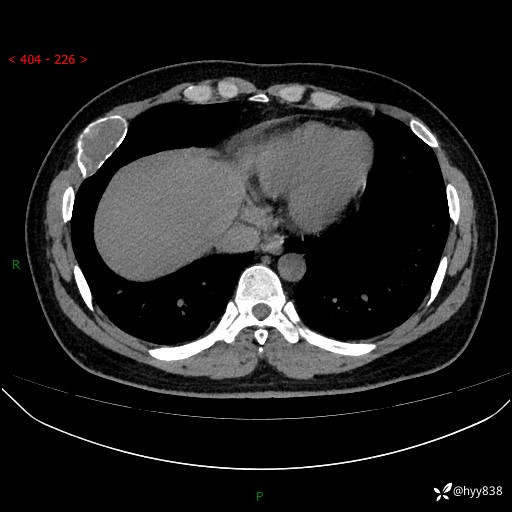

胸部CT平扫